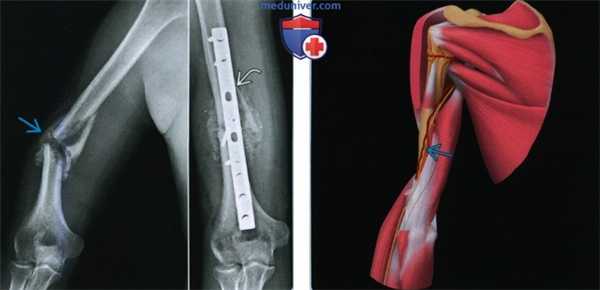

Рентгенограмма при переломе диафиза плечевой кости

(Слева) На боковой и передне-задней рентгенограммах правого плечевого сустава у женщины 62 лет с болью и деформацией после падения с высоты тела виден перелом средней трети диафиза плечевой кости с варусным отклонением >30°. Кроме того, она не могла разогнуть запястье. Пацинтке проведена успешная закрытая репозиция под анестезией, проведенной в связи с парезом лучевого нерва и варусным отклонением.

(Справа) На передне-задней рентгенограмме виден оскольчатый спиральный перелом плечевой кости. Перелом хорошо сросся в гильзовой повязке.

(Слева) На передне-задних рентгенограммах виден пациент, которому планируется лечение по поводу неправильно сросшегося перелома. Через три месяца после перелома (слева) образовалась мозоль, но с варусным 32° и задним 22° отклонением (не показано). Впоследствии было проведено оперативное вправление (справа) с наложением пластины и фиксации шурупами.

(Справа) На задней проекции левой руки близко показан лучевой нерв в диафизе плечевой кости. Среди пациентов с переломами диафиза плечевой кости у 16% наблюдается парез лучевого нерва, проявляющийся свисанием кисти. У большинства наступает улучшение после репозиции смещения и отклонения.